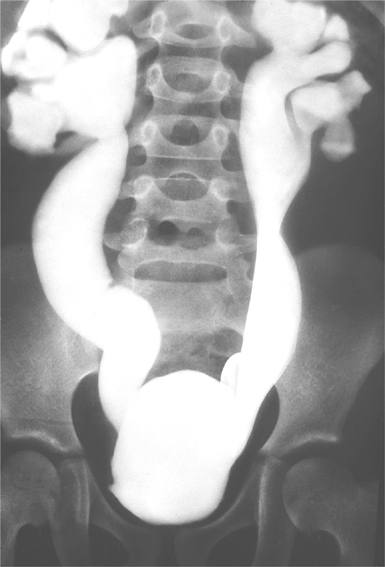

Q62.2 Врожденное расширение мочеточника [врожденный мегалоуретер]

Мегауретер (рентгенконстрастный снимок)